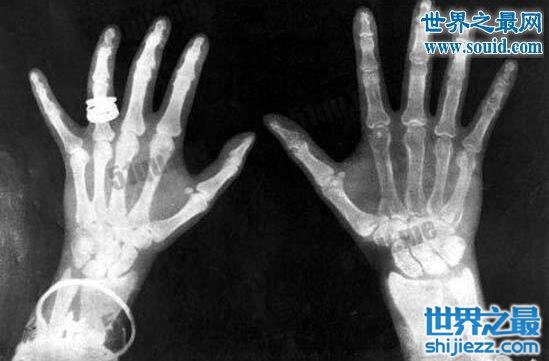

9、死人体重实验

这不是此类实验的正式名称,但有人认为这一名称仍能表现它的特性。1907年,美国马萨诸塞州哈佛山的邓肯·麦克杜格尔(Duncan MacDougall)医生将六个奄奄一息的病人放到一个特制的床榻上,在他们离开人世的那一刻测量其体重。根据麦克杜格尔实验结果,人死后的那一霎那的体重和死前比轻了21.3克。麦克杜格尔还在相同条件下对15条狗进行了测量,结果发现它们的体重并未发生可以察觉的变化。他通过这些实验得出了这样一个结论,即人的灵魂有重量,而狗确实没有灵魂。麦克杜格尔的实验曾发表于《纽约时报》和一些医学杂志上。

有趣的事实:麦克杜格尔在杂志上抱怨说他不能找到死于自然原因的狗,有人由此怀疑他为了实施这个实验毒死了几条狗。另外,这些实验还为一部名为《21克》的影片提供了创作灵感,该片由肖恩·潘担纲主演。